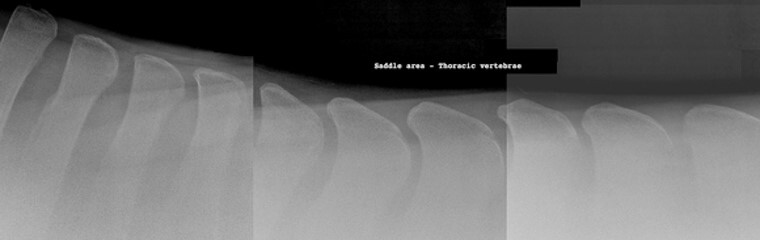

Most commonly acquired radiograph view used to image disease of dorsal spinous process

A

Laterolateral